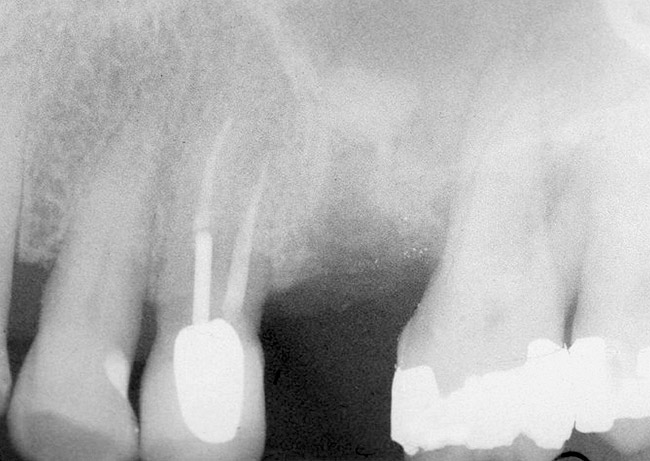

First, a periapical radiograph is taken to determine the amount of bone subantrally. It should be noted that a periapical film has an average error of 14%.23 Therefore, it is advantageous to take the radiograph in a manner that includes a marker (5-mm wide ball bearing) in order to be able to calculate the magnitude of radiographic error (Figure 1).

Figure 1  At tooth site No. 14, a periapical radiograph was taken with the long-cone paralleling technique. The radiographic ball marker measured 5.8 mm while its actual diameter is 5 mm. The enlargement is 0.8 mm, therefore the magnification error is 0.8/5 = 16%. By correcting for this error, a closer approximation of the amount of bone from the osseous crest to the sinus floor can be made.

Figure 1